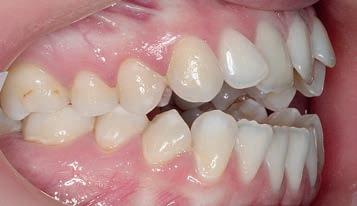

Figs. 1a–h: Initial situation: patient’s facial view (a-c); intraoral view (d-f); cephalometric X-ray (g); pantomograph X-ray (h).

A female, age 23 years, 5 months, presented for treatment exhibiting a moderate Class III malocclusion with negative overjet, proclined lower lip with flat supramentale sulcus, open bite and crowding in the lower arch. The treatment plan was to distalise the lower dentition into a Class I occlusion (Sagittal First) using the Carriere Motion CL III Appliance, then generate space to alleviate the lower arch crowding and close the bite, utilising light-force archwires in a passive, self-ligating system. While tongue trainers would be bonded in conjunction with the fixed appliances later in treatment, the patient would also engage in tongue training exercises to correct her improper